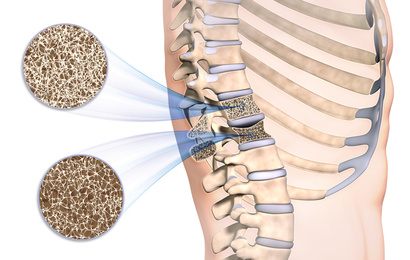

:background_color(FFFFFF):format(jpeg)/images/article/de/wirbelsaule/a1wjCWbEAeBhCqqodBbjHQ_Wirbels_ule_von_dorsal.png)